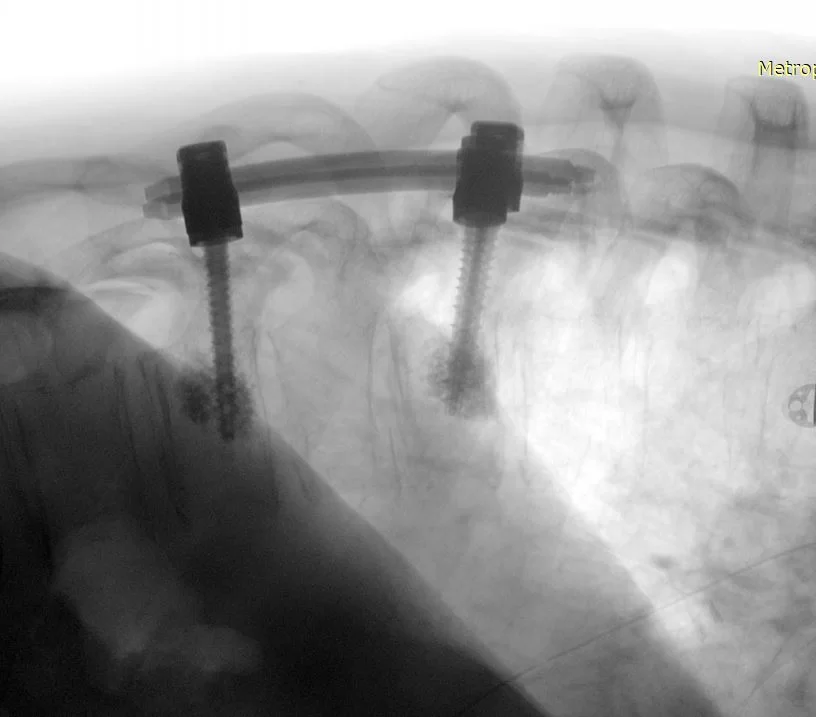

Διενεργήθη αποσυμπίεση του νωτιαίου μυελού μέσω πεταλεκτομίας και αφαίρεσης του ενδοκαναλικού τμήματος του όγκου και στη συνέχεια διαδερμική σπονδυλοδεσία με έγχυση οστικού τσιμέντου στα σπονδυλικά σώματα Θ9-Θ11

Στο συγκεκριμένο περιστατικό συνδυάστηκαν η ανοιχτή μέθοδος της πεταλεκτομίας για την αφαίρεση του ενδοκαναλικού τμήματος του όγκου και την αποσυμπίεση του νωτιαίου μυελού, με τη διαδερμική τεχνική της σπονδυλοδεσίας. Οι βίδες τοποθετήθηκαν με τη βοήθεια νευροπλοηγού το οποίο δίνει στο χειρουργό τη βεβαιότητα της απόλυτης ακρίβειας. Η διαδερμική τοποθέτηση των βιδών κράτησε την τομή μικρή, μειώνοντας σημαντικά τον μετεγχειρητικό πόνο και τον κίνδυνο φλεγμονής, επιτρέποντας στον ασθενή την άμεση κινητοποίηση και έξοδο από το νοσοκομείο. Η ενίσχυση των σπονδυλικών σωμάτων με οστικό τσιμέντο είχε πολλαπλό ρόλο: αφενός βοηθά στη σταθερότητα της σπονδυλοδεσίας (επιτρέποντας μας να έχουμε καλή στήριξη με “μικρή” σπονδυλοδεσία), αφετέρου προσέφερε σταθερότητα στον Θ9 σπόνδυλο ο οποίος είχε προσβληθεί από νόσο.